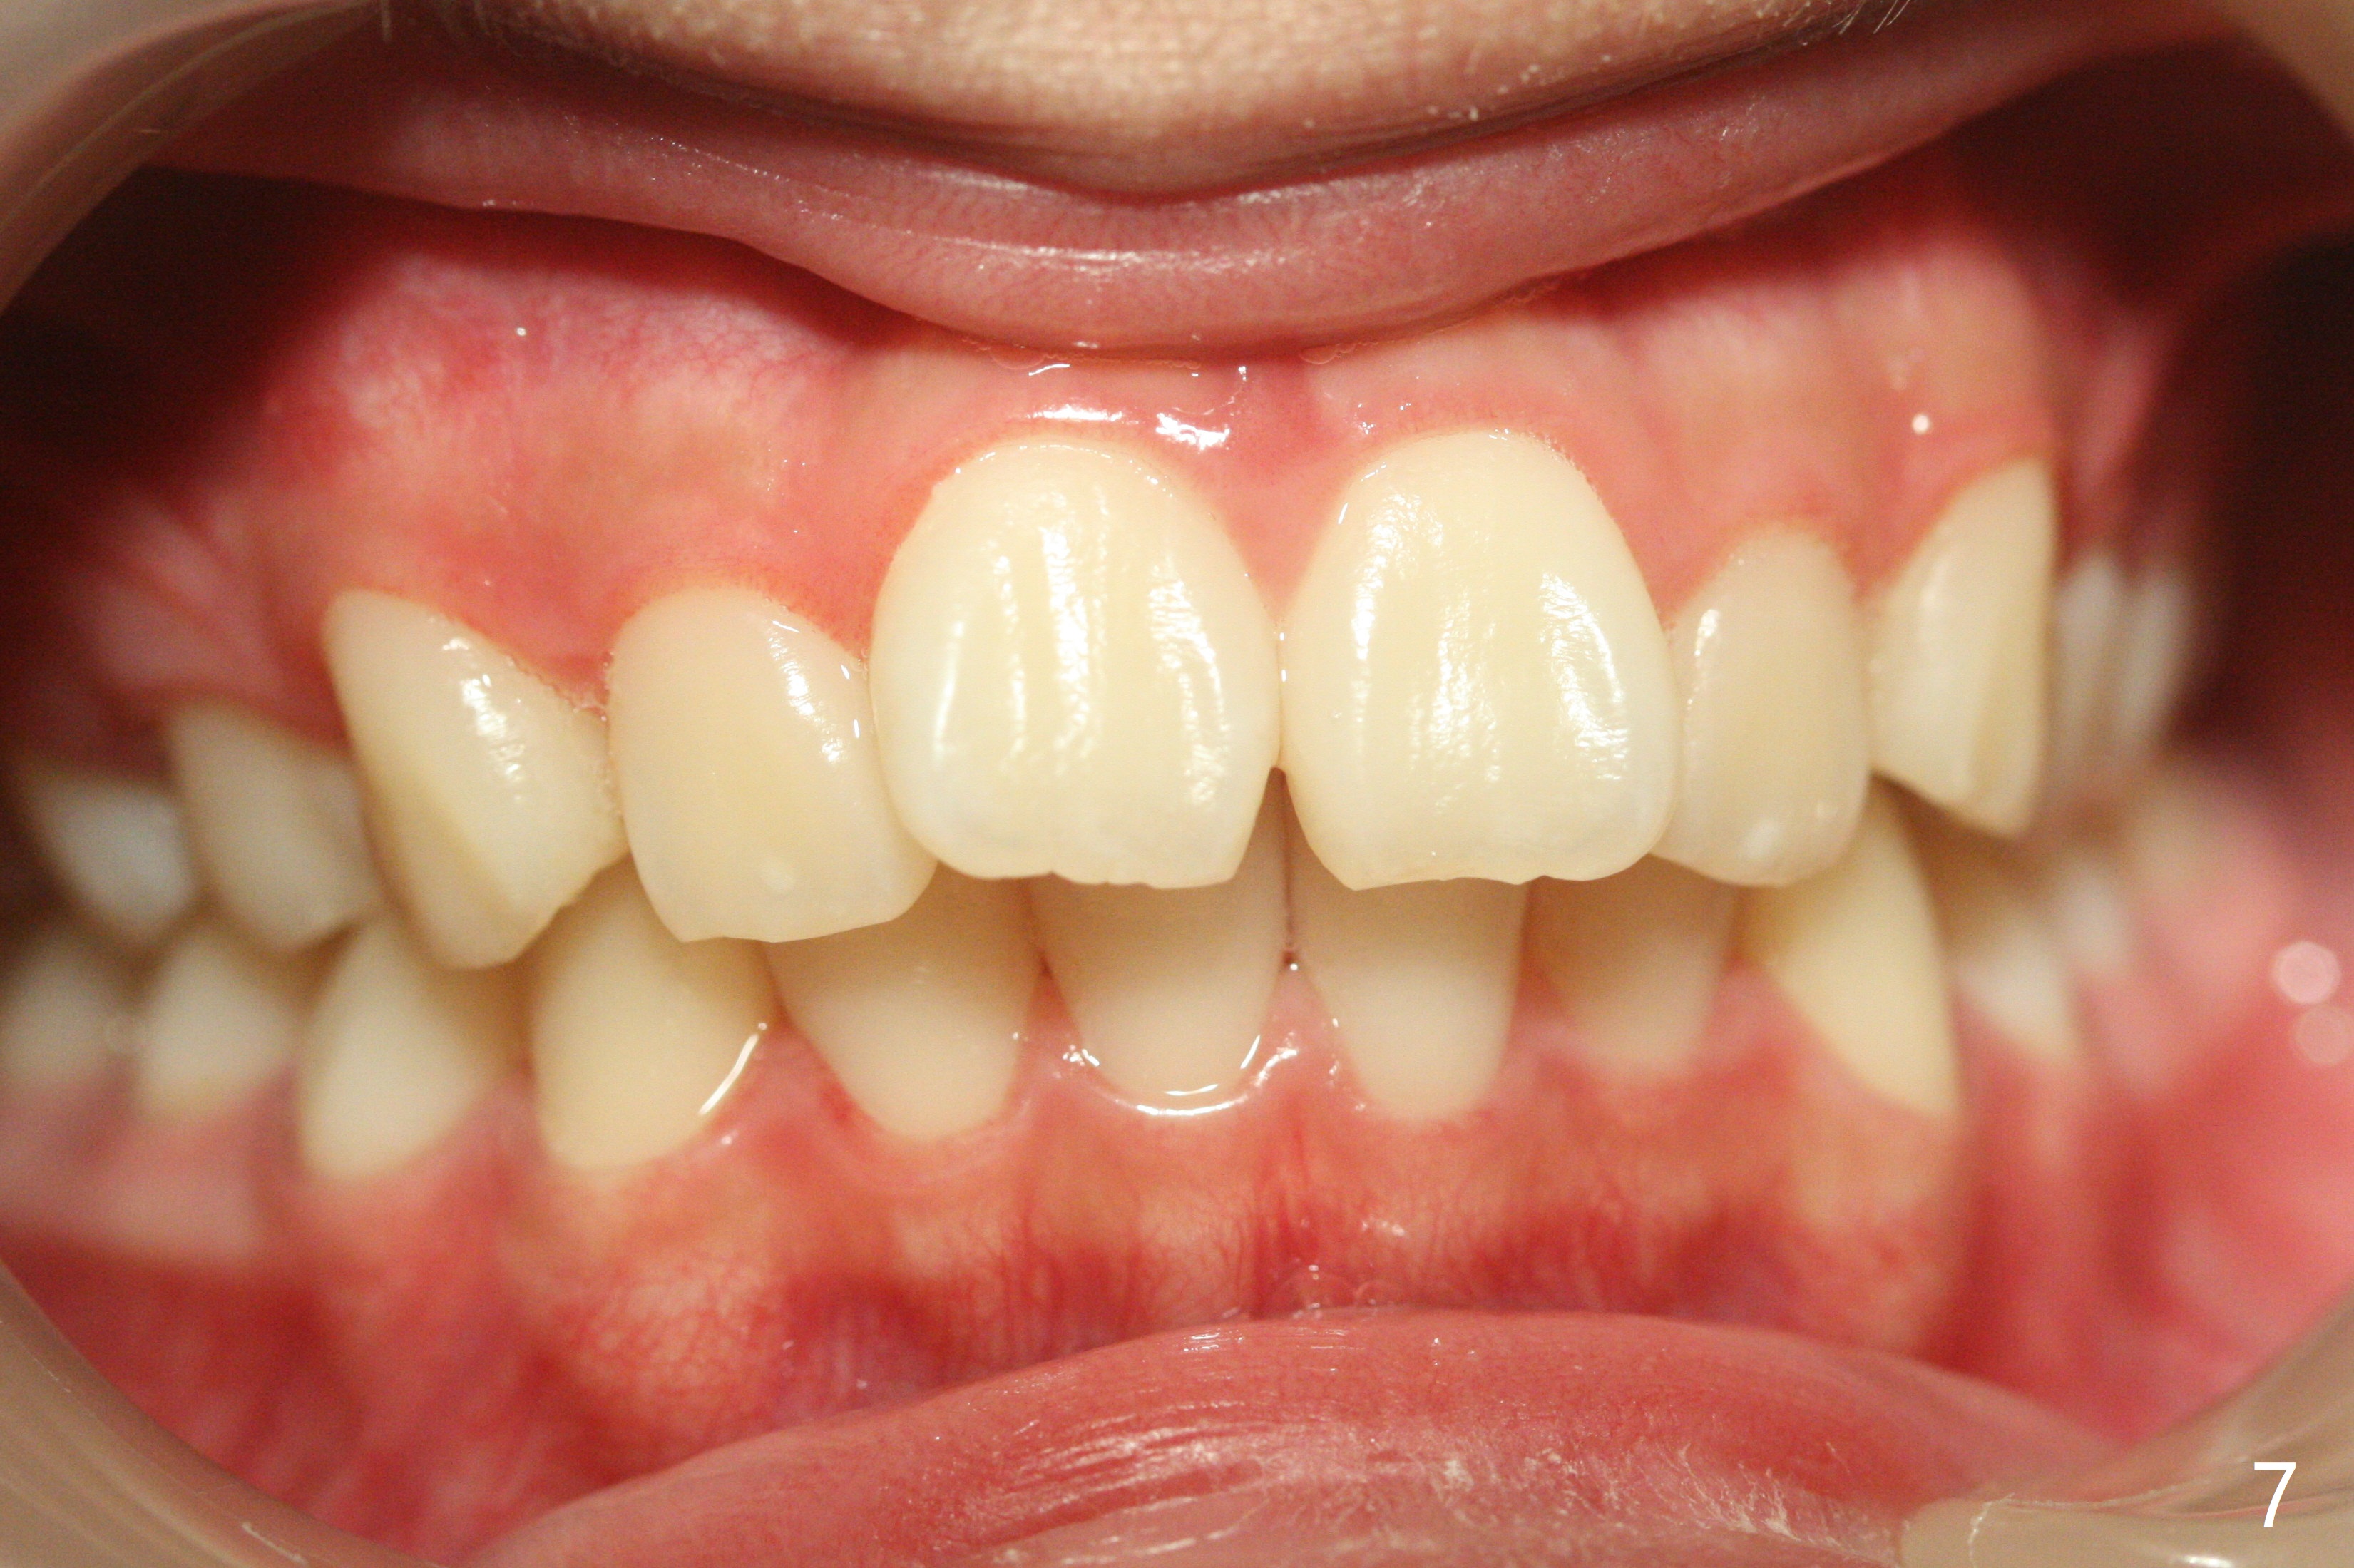

A 12-year-old woman has Class I facial profile (Fig.1-4,12,13) and apparently Class II Division I malocclusion (Fig.6-11). Start Class II retraction as early as possible to take advantage of the upper and lower posterior diastemata (Fig.9,11 (in fact there is no diastema)). LL7 impaction is noted immediately prebanding (Fig.14). Surgical access is pending.